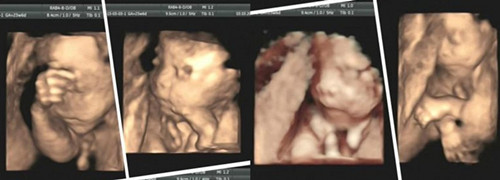

四维彩超的应用,他可多角度观察宫内胎儿的生长发育情况,对胎儿的体表进行检查,如唇裂,脊柱裂,大脑,肾,骨骼发育不良等,能为胎儿先天性体表畸形和先天性心脏疾病提供科学依据。蕞大的优势就是高清,排畸率比较高。所以四维彩超的应用,将有可能发生的悲剧降至蕞轻,为准父母的选择提供科学依据,同时也助准父母对孩子的健康问题做好心理准备